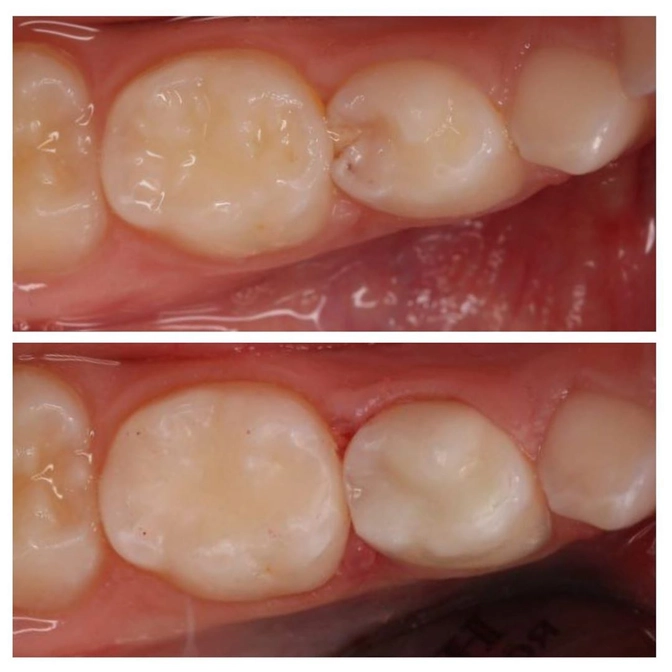

Ребенку 6 лет.

Пришел на плановый осмотр к доктору Марии Штельмах.

Сделали рентген и что увидели?

Скрытый кариозный процесс! Посмотрите снимок в карусели, и сами увидите, насколько глубоко проник кариес.

Первичный осмотр и снимок были сделаны в конце марта.

Спустя 1,5 месяца мы уже видим кариес без рентгена невооруженным глазом.

Вот так быстро протекают у детей кариозные процессы!

Полость стала намного глубже.

Диагноз - пульпит.

Зуб пролечили и восстановили пломбировочным материалом.